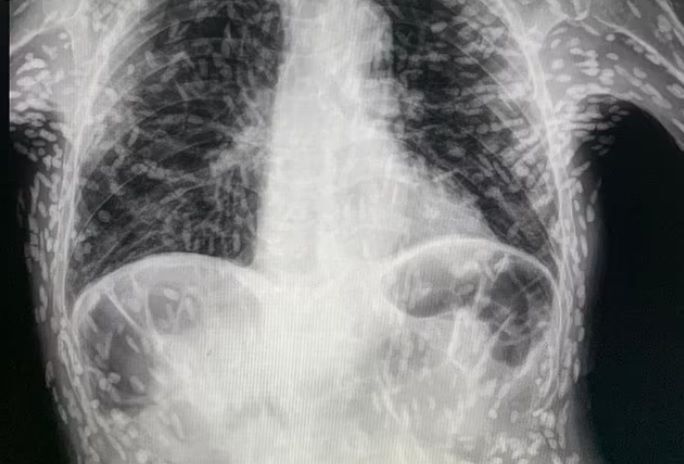

이 문서에서 언급된 엑스레이 사진과 관련된 환자의 경우, 의료진은 해당 환자가 특별한 치료를 받지 않아도 된다고 밝혔습니다. 만약 뇌나 척수, 눈에 이상이 없다면 추가적인 치료가 필요하지 않을 수 있습니다. 또한, 사진 속의 유충들은 석회화되어 생존할 수 없는 상태이므로 특별한 조치가 필요하지 않습니다. 그러나 해당 환자의 뇌에 낭종이 있는지 확인하기 위해 MRI 검사를 기다리고 있다고 전해졌습니다. 따라서, 환자는 의료진의 조언에 따라 추가 검사를 받아야 하며, 이를 통해 건강 상태를 정확히 판단할 수 있습니다.